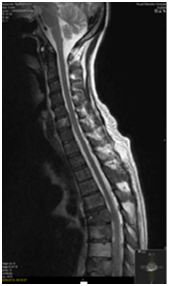

An MRI Whole spine was performed following his PET-CT given the extent of vertebral disease. Abuttment but not compression of the cord at the level of T6 was seen (Figure 5). Two weeks following this patient developed some neurological symptoms attributable to progression at this site. Multiple wedge fractures and imminent compression of the cord was seen. A neurosurgical opinion was sought and this patient was deemed not to be for surgical intervention. Twenty Gray in 5 fractions of palliative radiotherapy was delivered to T5, T6 and T7 vertebrae.

Figure 5 Expansile metastases including at T6 narrowing the spinal canal and indenting the cord on

MRI spine.